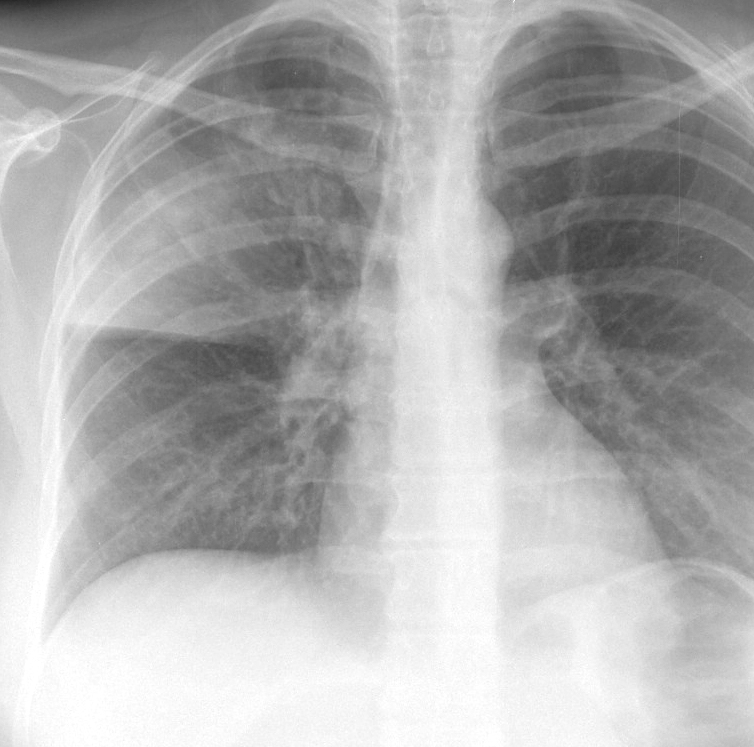

Case 7 RUL pneum PA